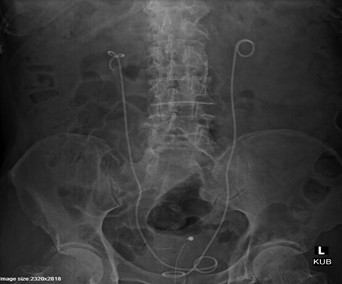

Fig (1): KUB X-ray image of DJ stenting

A 73-year-old male presented with complaints of fever with chills and painful micturition for two days, along with decreased alertness at the onset of fever. He was a known case of Type 2 Diabetes Mellitus, Hypertension, Parkinson’s Disease, and Benign Prostatic Hyperplasia and was on regular medications. On admission, the patient was hemodynamically stable. Initial clinical evaluation suggested chronic prostatitis, and empirical therapy with Inj. Teicoplanin 400mg and Tab. Methenamine hippurate 1gm was initiated. However, due to worsening clinical and laboratory parameters, further evaluation was carried out, and the diagnosis was revised to complicated urinary tract infection with acute pyelonephritis. Antibiotic therapy was escalated with Inj. Amikacin 500mg and Inj. Fosfomycin 6gm. Urine culture revealed growth of multidrug-resistant Pseudomonas aeruginosa. In view of suspected obstructive uropathy, a left-sided DJ stenting procedure was planned and successfully performed. During hospitalization, a drug interaction between Tab. Methaclear 1gm and Tab. Syndopa 110mg was identified, presenting as dizziness, and appropriate dose modification was done. Following intervention and targeted therapy, the patient showed significant clinical improvement and clinically stable after six days.

Complicated urinary tract infections are commonly encountered in elderly patients with comorbid conditions such as diabetes mellitus and urinary tract obstruction and are associated with increased morbidity.1,6 Diabetes mellitus predisposes patients to infections through impaired immune responses, glycosuria, and increased bacterial adherence, leading to more severe and recurrent infections.3,7 Similarly, benign prostatic hyperplasia contributes to urinary stasis, which facilitates bacterial colonization and ascending infection. Acute pyelonephritis occurs when pathogens ascend from the lower urinary tract to the kidneys, resulting in inflammation of the renal parenchyma and systemic manifestations.7 In this case, the isolation of Pseudomonas aeruginosa is clinically significant due to its multidrug resistance and association with healthcare-related infections, which complicates treatment strategies. The markedly elevated CRP levels and leukocytosis observed in this patient indicate a severe inflammatory response. Early initiation of broad-spectrum antibiotics followed by culture-guided therapy is essential in managing such infections.8 In this case, the use of Amikacin and Fosfomycin provided effective coverage against Gram-negative organisms. Although Teicoplanin is known to have synergistic effects with aminoglycosides against Gram-positive organisms, its role in this case was primarily empirical. An important aspect of management was the timely placement of a DJ stent, which relieved obstruction and facilitated drainage of infected urine, significantly improving clinical outcomes.

This case highlights how complicated urinary tract infections in elderly patients with comorbidities can quickly progress to severe conditions like pyelonephritis. The combination of Amikacin and Fosfomycin provided effective Gram‑negative coverage, while empiric Teicoplanin offered additional support through its potential synergistic activity with aminoglycosides. Timely DJ stent placement was crucial, relieving obstruction and enabling adequate drainage, which significantly improved clinical outcomes. Overall, early diagnosis, appropriate antimicrobial therapy, and prompt urological intervention are essential, especially when managing multidrug‑resistant organisms such as Pseudomonas aeruginosa.